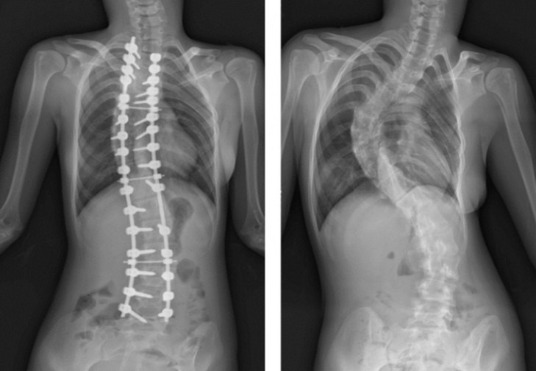

根據美國骨科醫學會(AAOS,2019)臨床指引,當脊椎彎曲角度(Cobb angle)超過45-50度,或已造成明顯變形、疼痛、呼吸受限時,建議由骨科醫師評估是否進行手術矯正。然而,手術屬侵入性治療,須考量年齡、成長潛力與風險,並非所有患者皆適合。

圖右,15歲男生,極重度脊椎側彎,肋骨、胸廓嚴重變形

圖左,脊椎側彎矯正手術後